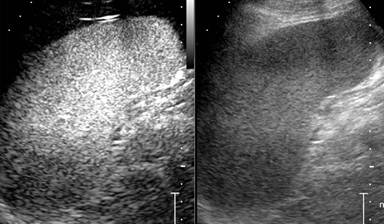

After removal of all needles, a CT scan with iv contrast medium administration was performed to evaluate the absence of vascular complications given the relative proximity of the celiac trunk; it revealed a vasoconstriction of splenic artery associated with the presence of multiple small spleen defects of perfusion (Figure 2ab), that were not present at CT scan performed before treatment (Figure 3). The day after the procedure the patient underwent a contrast enhanced ultrasound (CEUS) that did not revealed ischemic areas in the splenic parenchyma and showed normal patency of splenic artery (Figure 4). During the hospital stay, complete blood counts and electrolyte levels were monitored and liver function tests were performed twice a week.

Figure 3. CT scan revealed splenic artery regularly patent but entirely trapped in the tumor. |

Figure 4. CEUS not revealed ischemic areas in the splenic parenchyma. |